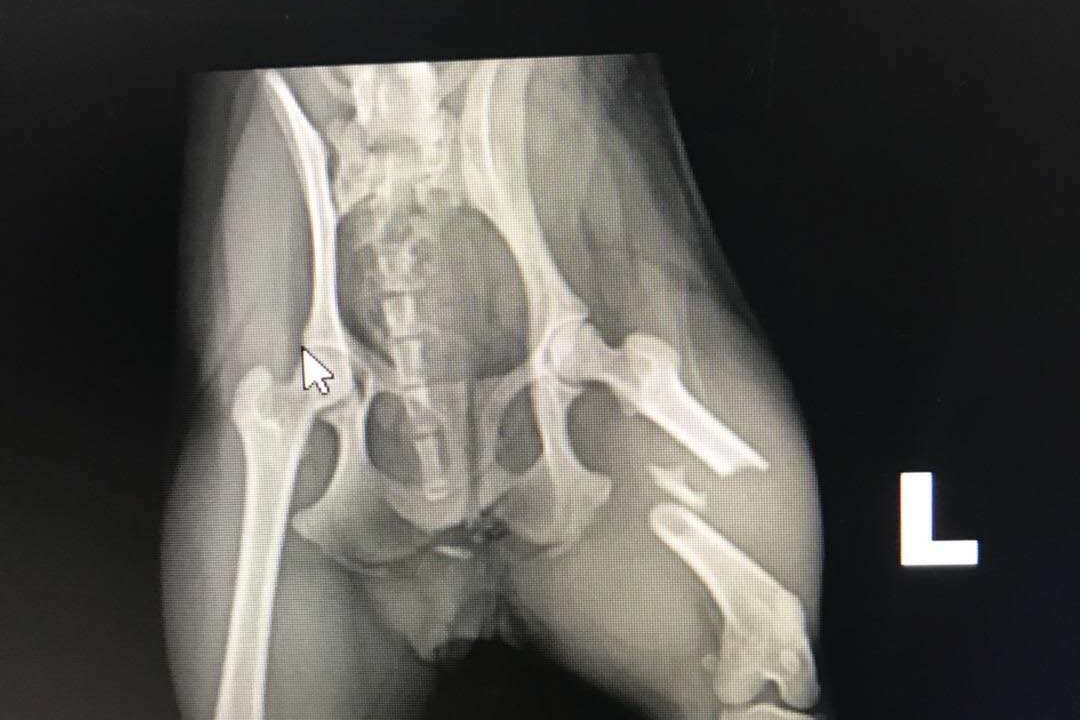

Hi. I’m Bao Bao. I was homeless and hungry on the streets of Beijing. I was so sad. I missed my mama and I was always hungry. Somehow my tail got chopped off and my leg was broken. I’ve been running around with a broken legs for a long time. There are always many other homeless dogs around me. I’m just a little girl , so I had to be carful not to get attacked. Also , I would have to hide when I saw the police come around because they would take us dogs away and off the streets. They said they were cleaning up the streets, but everyone knows they kill them. I am little so I can hide. I was hiding in the grass one day and I saw some people taking a family of mama, papa and two babies and put them in a van. I watched them go one by one back and forth. I wished I had a family and I realized they were rescuing them, so I ran after them and tugged at their feet for them to take me too. I was saying “save me too. Just one more ! I’m small. I can fit in your van. “ They didn’t understand what I was saying because they don’t speak dog, but they knew my desperation. This was my only chance. China is a big place for a little dog like me and it’s not every day compassionate dog rescuers come your way. They took heart with me and tossed me in the van. Now they flew me to USA so I can get my broken leg fixed. Having surgery today and will recover at my fosters house. I am very happy now. I just need my leg fixed and to be spayed later and have medicine. I love my rescuers I feel so lucky. ❤️We are a non profit rescue. Animalofworldfoundation.org. We get some donations , but mostly we pay for out of our own pockets so we are trying to raise money for Bao Bao to have surgery. We rescue dogs from the streets of Beijing mainly. Many of them have broken legs or large gashes and no tails and so we save one or as many as we can at a time and send them to USA and get them medical treatment. Bao Bao has surgery today approximately $1530 plus needs spay and 4 extractions teeth and Medicine. Any extra will go to help the next dog. The surgery was actually $4000 and Dr Paul gave us a discount to make it $1500. I am a volunteer and animal activist and am raising funds for Animal of World Foundation for this little dog Bao Bao. This division of Animal of World Foundation rescues homeless and abused dogs from the streets of China. Mainly Beijing. Thank you